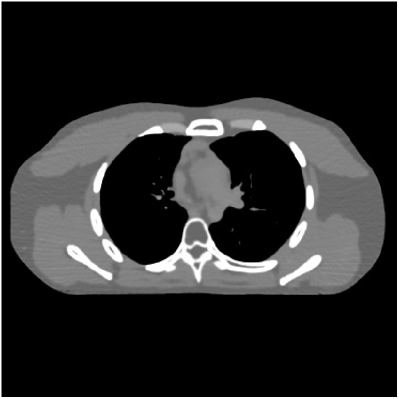

This section compares the reconstruction quality and runtime among the proposed MBIR method, PWLS-ST-, and other three MBIR methods, PWLS-EP, PWLS-DL, and PWLS-ST-. Table I shows that, for both 2D and 3D sparse-view CT reconstructions of the XCAT phantom, the proposed PWLS-ST- model outperforms PWLS-EP and PWLS-ST- in terms of RMSE. In addition, PWLS-ST- using a square transform (of size ) achieves lower RMSE than PWLS-DL using an overcomplete dictionary (of size ) for 2D sparse-view reconstructions. Fig. 3(a) and Fig. 4 show the reconstructed images for 2D and 3D phantom experiments, with different reconstruction models and different number of views. (See the corresponding error maps in the supplement.) The proposed PWLS-ST- consistently gives more accurate image reconstructions compared to other MBIR methods. Specifically, PWLS-ST- has smaller errors in the heart region (see zoom-ins in Fig. 3(a)) of 2D reconstructions than PWLS-DL and PWLS-ST-. In addition, compared to PWLS-ST-, PWLS-DL and PWLS-ST- have some ringing artifacts around the edges with high transition, e.g., edges between air and soft tissues. (See a comparison of profiles of PWLS-ST- and PWLS-ST- in the supplement.) In particular, PWLS-ST- and PWLS-DL give more visible ringing artifacts for 2D reconstruction from fewer views, and PWLS-ST- has these ringing artifacts for 3D reconstructions regardless of the number of views (see zoom-ins in Fig. 4). Table II reports runtimes of different MBIR methods in reconstructing the -views XCAT phantom scan. (FBPConvNet is a non-MBIR method and its runtime for processing a image is approximately one second with a TITAN Xp GPU.) While providing better reconstruction quality, the proposed Algorithm 1 of PWLS-ST- has shorter runtime compared to the algorithms of PWLS-DL and PWLS-ST- in Section III-A. Similar to the PWLS-EP algorithm, the reconstruction time of the PWLS-DL, PWLS-ST-, and PWLS-ST- algorithms can be further reduced by using ordered subsets [51].

| (b) 3D axial cone-beam CT experiments |

This section compares the generalization capabilities between the proposed MBIR method, PWLS-ST-, and a denoising deep NN, FBPConvNet [14], that are trained from the phantom data; in particular, we tested the trained PWLS-ST- and FBPConvNet models to phantom and clinical scan data. The results in Fig. 6 show that the non-MBIR FBPConvNet method has higher overfitting risks, compared to the proposed PWLS-ST- MBIR method. When tested on clinical scan data, PWLS-ST- achieves much more accurate reconstruction, compared to FBPConvNet. See Fig. 6(b). When tested on phantom data, FBPConvNet generates more unnatural features as the number of views reduces, although it gives lower RMSE values compared to PWLS-ST-. See zoom-ins in Fig. 6(a). The FBPConvNet results above correspond to those in the recent work [16] that FBPConvNet [14] generated some unexpected structures.